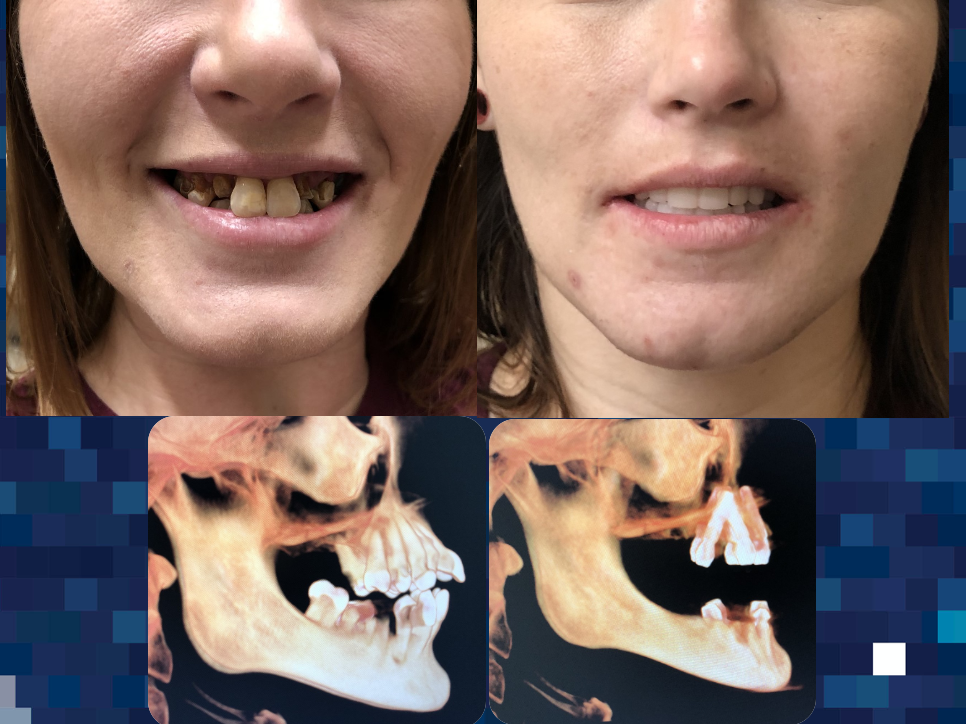

World-Class Expert Perinasal, Pterygoid, and Zygomatic Implants

Dr. Cesar Guerrero has spent 30 years renewing lives by offering specialized surgical care that improves quality of life and relieves pain. His extensive training with top doctors across six continents makes him an expert in his field. One of Dr. Guerrero’s offered services are Perinasal, Pterygoid, and Zygomatic Implants, which are advanced solutions designed for patients with severe bone loss, offering a stable, effective foundation when traditional implants are not an option.